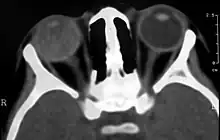

Imaging studies such as ultrasonography (US), Computerized Tomography (CT) and Magnetic Resonance Imaging (MRI) can aid diagnosis. On ultrasound, Coats' disease appears as a hyperechoic mass in the posterior vitreous without posterior acoustic shadowing; vitreous and subretinal hemorrhage may often be observed.[7][8]

On CT, the globe appears hyperdense compared to normal vitreous due to the proteinaceous exudate, which may obliterate the vitreous space in advanced disease. The anterior margin of the subretinal exudate enhances with contrast. Since the retina is fixed posteriorly at the optic disc, this enhancement has a V-shaped configuration.[2]